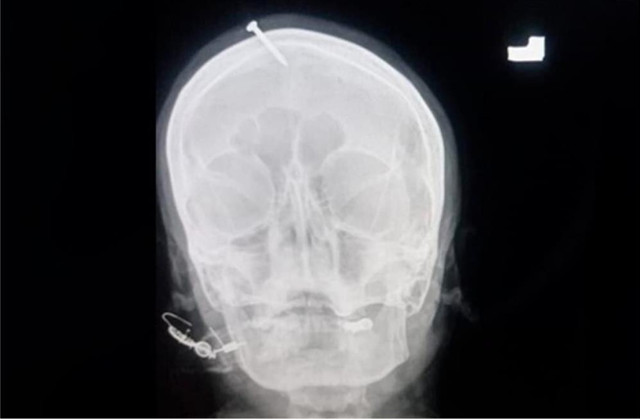

Şifacının tavsiyesine uyan kadın daha sonra alnında 5 santimetrelik çivi ile Lady Reading Hastanesi'ne başvurdu. Kadını tedavi eden Nörolog Haider Suleman, çivinin kadının kafatasına girmesine rağmen beynine ulaşmadığını ifade etti.

Suleman basına verdiği demeçte, kadının kendisi ile aynı bölgede yaşayan başka bir kadının kafasına çivi çaktığını ve ultrasonda kız çocuğu olarak gözüken bebeğinin erkek olarak dünyaya geldiğini kendisine anlattığını aktardı. Polis, söz konusu olayı kadının röntgen filmlerinin sosyal medyada gündem haline gelmesi ile öğrenirken, olayla ilgili soruşturma başlatıldı. Şifacının arandığını belirten polis, ayrıca kadını tedavi eden doktorun olayı neden polise bildirmediğinin de araştırılacağını aktardı.